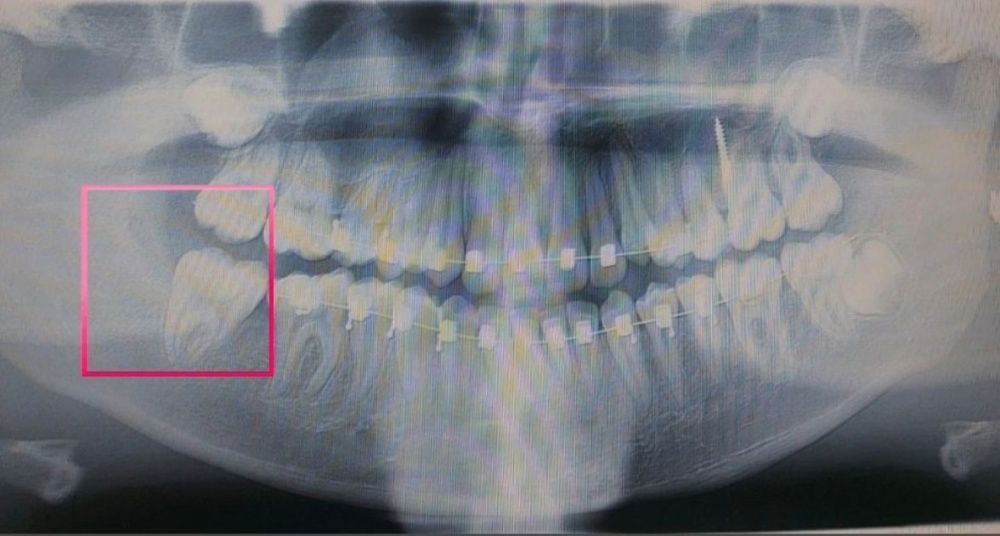

Стоматологом хирургом под местной анестезией проведено удаление зачатка зуба мудрости. Одномоментно установлен ортодонтический минивинт в ветвь нижней челюсти.

Через 1,5 месяца жевательный зуб 4.7 поставлен на свое место. Ортодонтический винт снят.

Пациентка продолжается лечение с помощью системы брекетов.